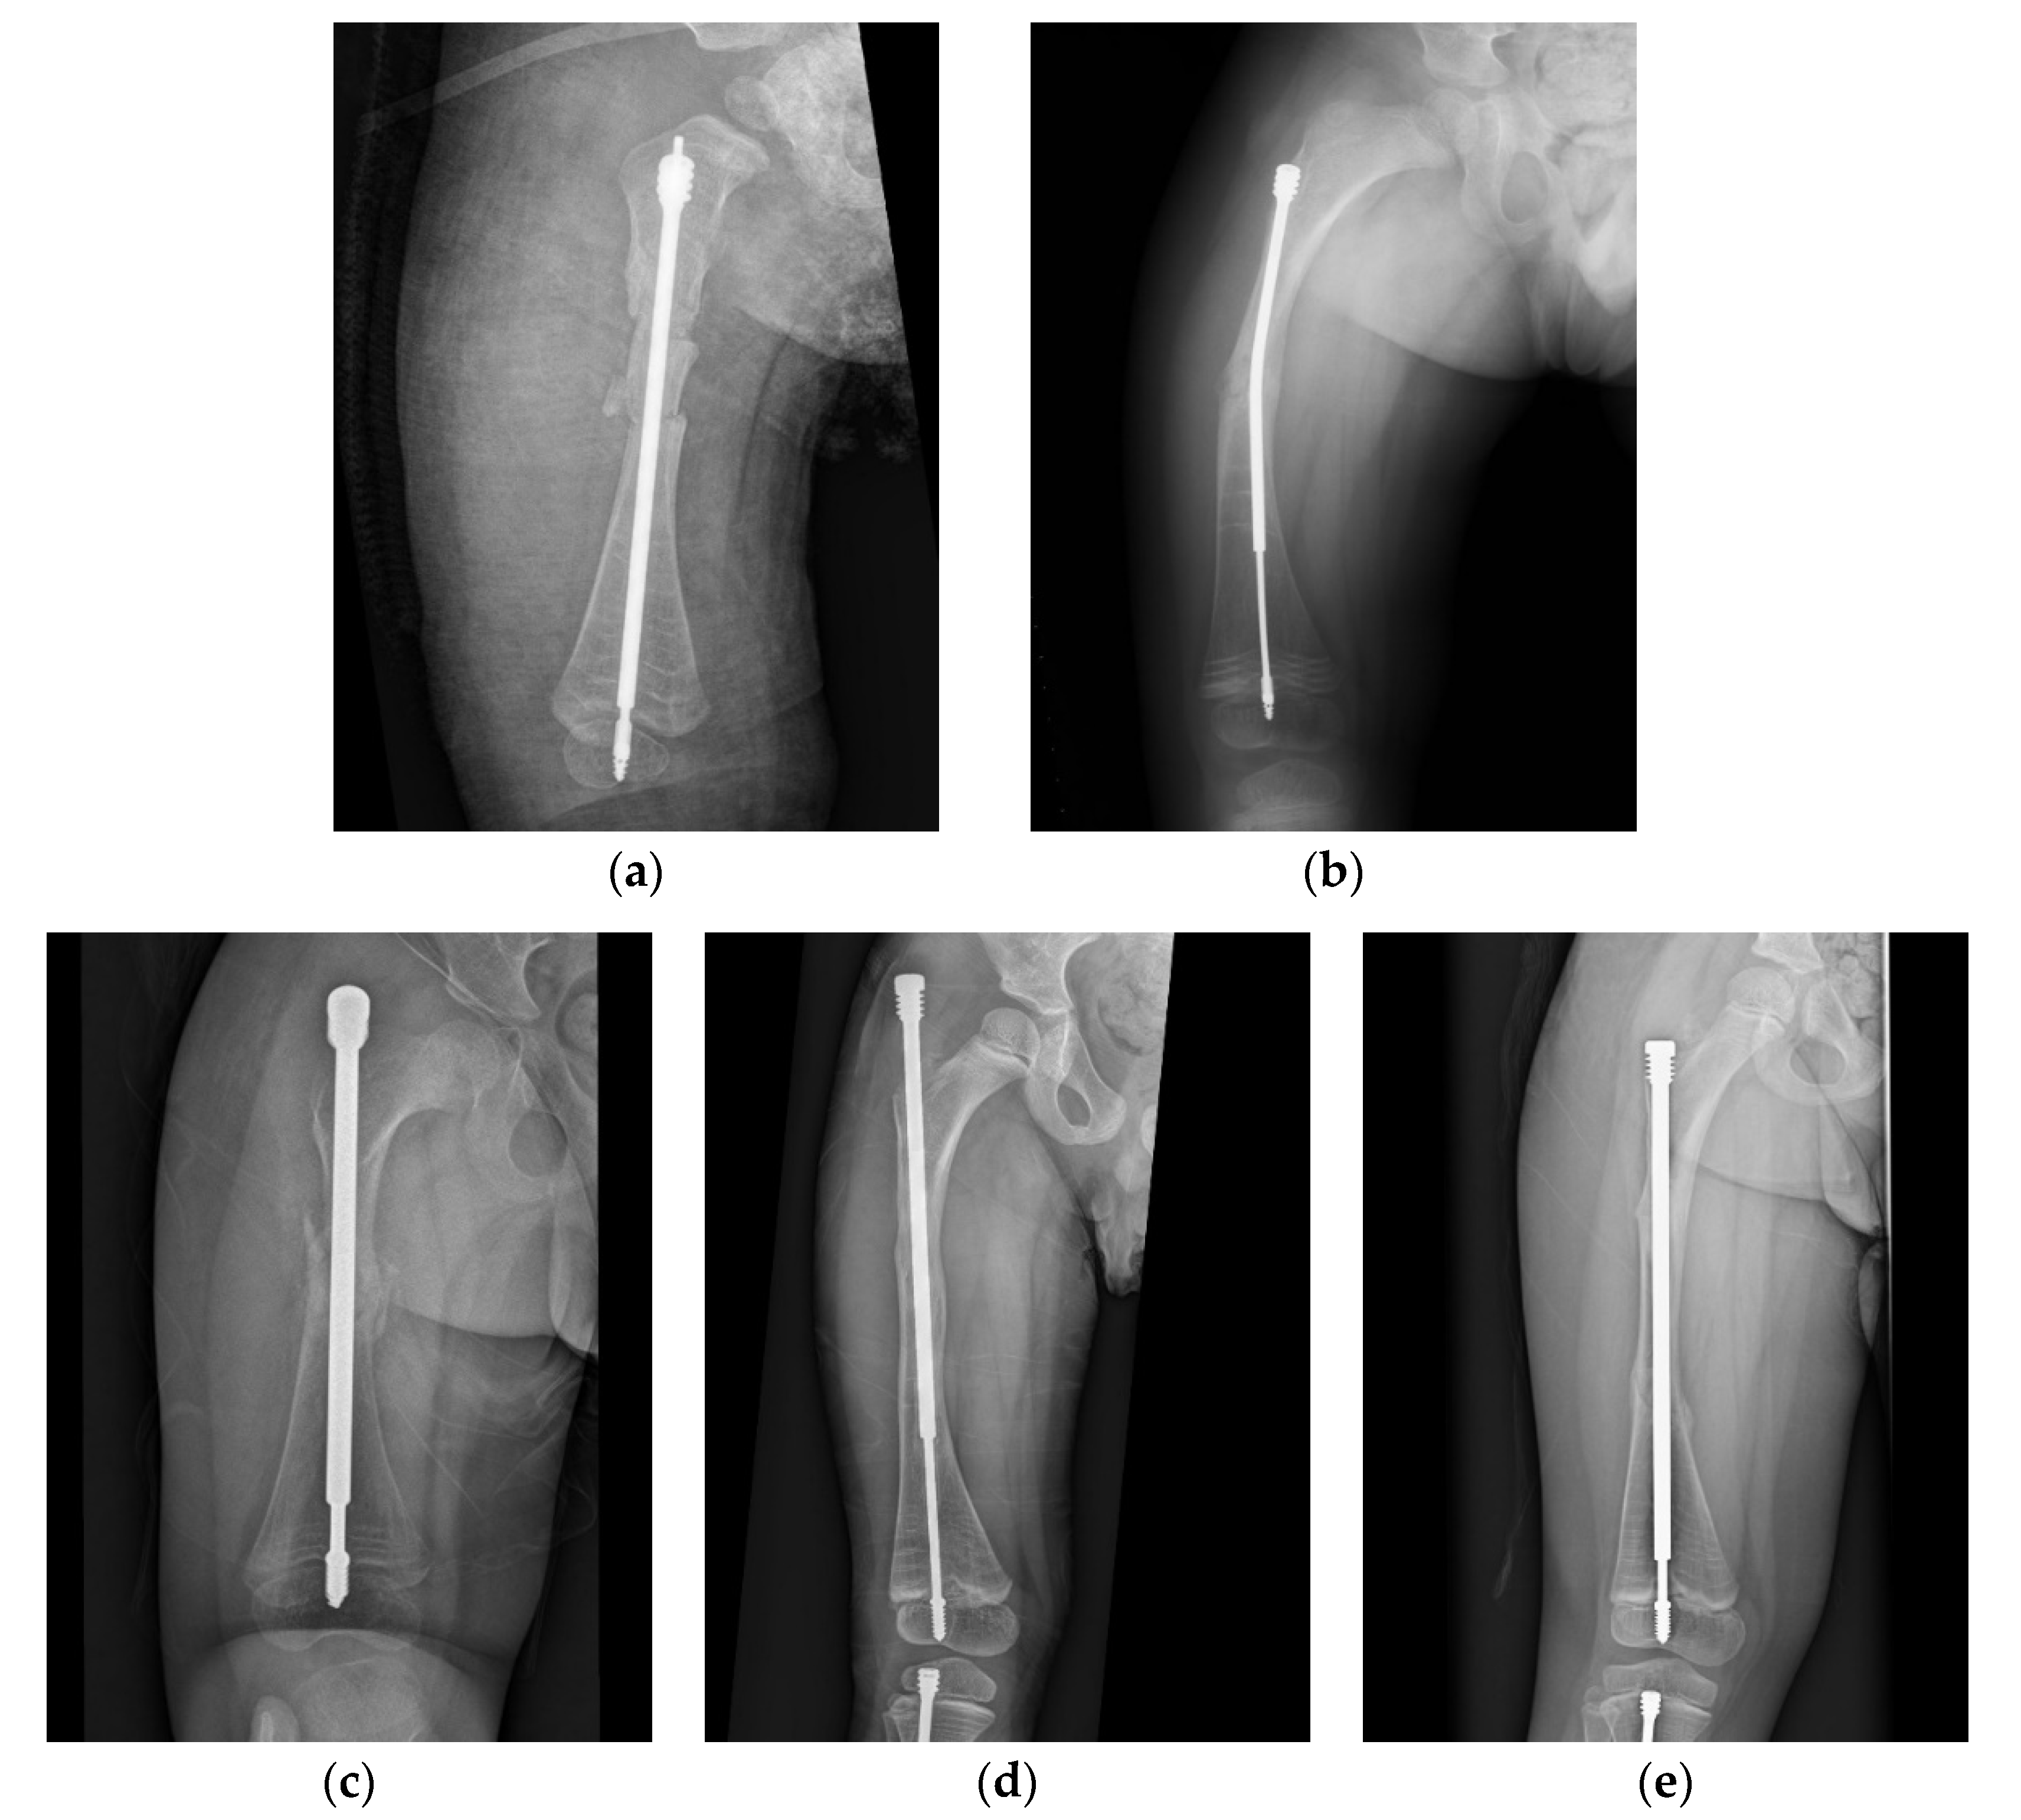

In a case of a 4-year-old female with type III OI (Figure 1), the position of the male component was quite central in the distal epiphysis on both anteroposterior and lateral views. However, there was insufficient purchase of the male component tip (Figure 1a). If the threads end just around the physis instead of beyond it (Figure 1b), distal dislodgement would occur along with growth of the limb (Figure 1c). However, this raises the question of how to ensure sufficient depth of the male implant intraoperatively. We suggest the following steps: First, center the male component at the center of the distal epiphysis as far as possible so that the thickest epiphysis is purchased. The thread of the male component needs to be fully submerged into the epiphysis, and the flange of the nail must exceed the physis, or at least stop at the level of the physis. If the distal epiphysis of the tibia is small, the tip of the nail may reach the subchondral area to ensure that the whole thread goes through the physis (Figure 2). Since the distal epiphysis of the femur is larger than the distal epiphysis of the tibia, there is a relatively lower risk of distal dislodgement in the femur (tibia 4, femur 1 in our series) due to sufficient distal purchase.

Figure 1. Anteroposterior (AP) view radiograph of the lower leg of a 4-year-old female post FD nail implantation. (a) The position of the nail was quite central in the distal epiphysis. (b) Looking closely, there was insufficient purchase of the nail. (c) As the patient grew, the male component migrated (distal tibial nail pulled out of the epiphysis) 1.5 years after implantation.